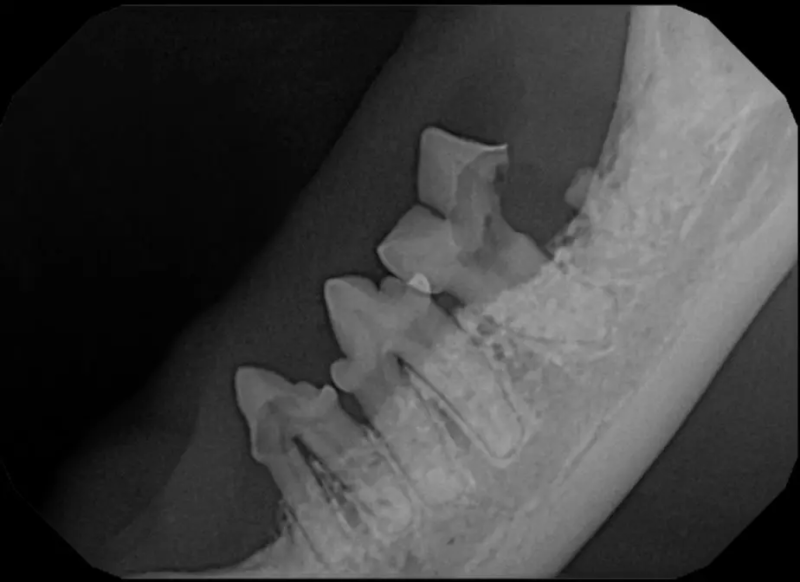

Crowns

Crowns are placed on fractured teeth to provide the strength to the tooth structure. This is often performed on working dogs or pets who need their teeth for specific activities. The crowns are made of non-precious metal and require one episode of anesthesia to prepare the tooth and create the molds for crown fabrication, and a second anesthetic episode to fit and cement the crowns.